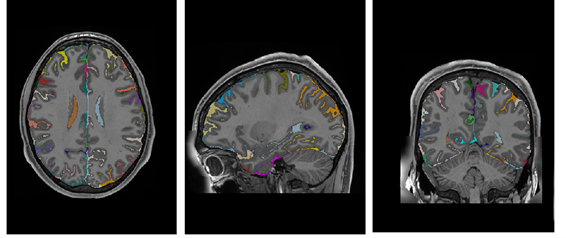

Data Records

Refer to caption

Figure 12: From Top to bottom: Average T1w MRI template, average T2w MRI template, average WMn MRI template and majority voting atlas labels at substructure resolution.

holiAtlas represents a comprehensive, multimodal, and ultra-high-resolution MRI-based atlas of the human brain anatomy. This atlas was constructed by fusing data from various local protocols with corresponding scales, resulting in a densely labeled protocol. The creation involved averaging images and segmentations from 75 healthy subjects, employing T1w, T2w, and WMn MRI contrasts at a 0.125 mm3 resolution. This atlas offers a holistic view of the brain’s anatomy at different levels and scales, providing a valuable resource for segmentation methods, research, and educational purposes.